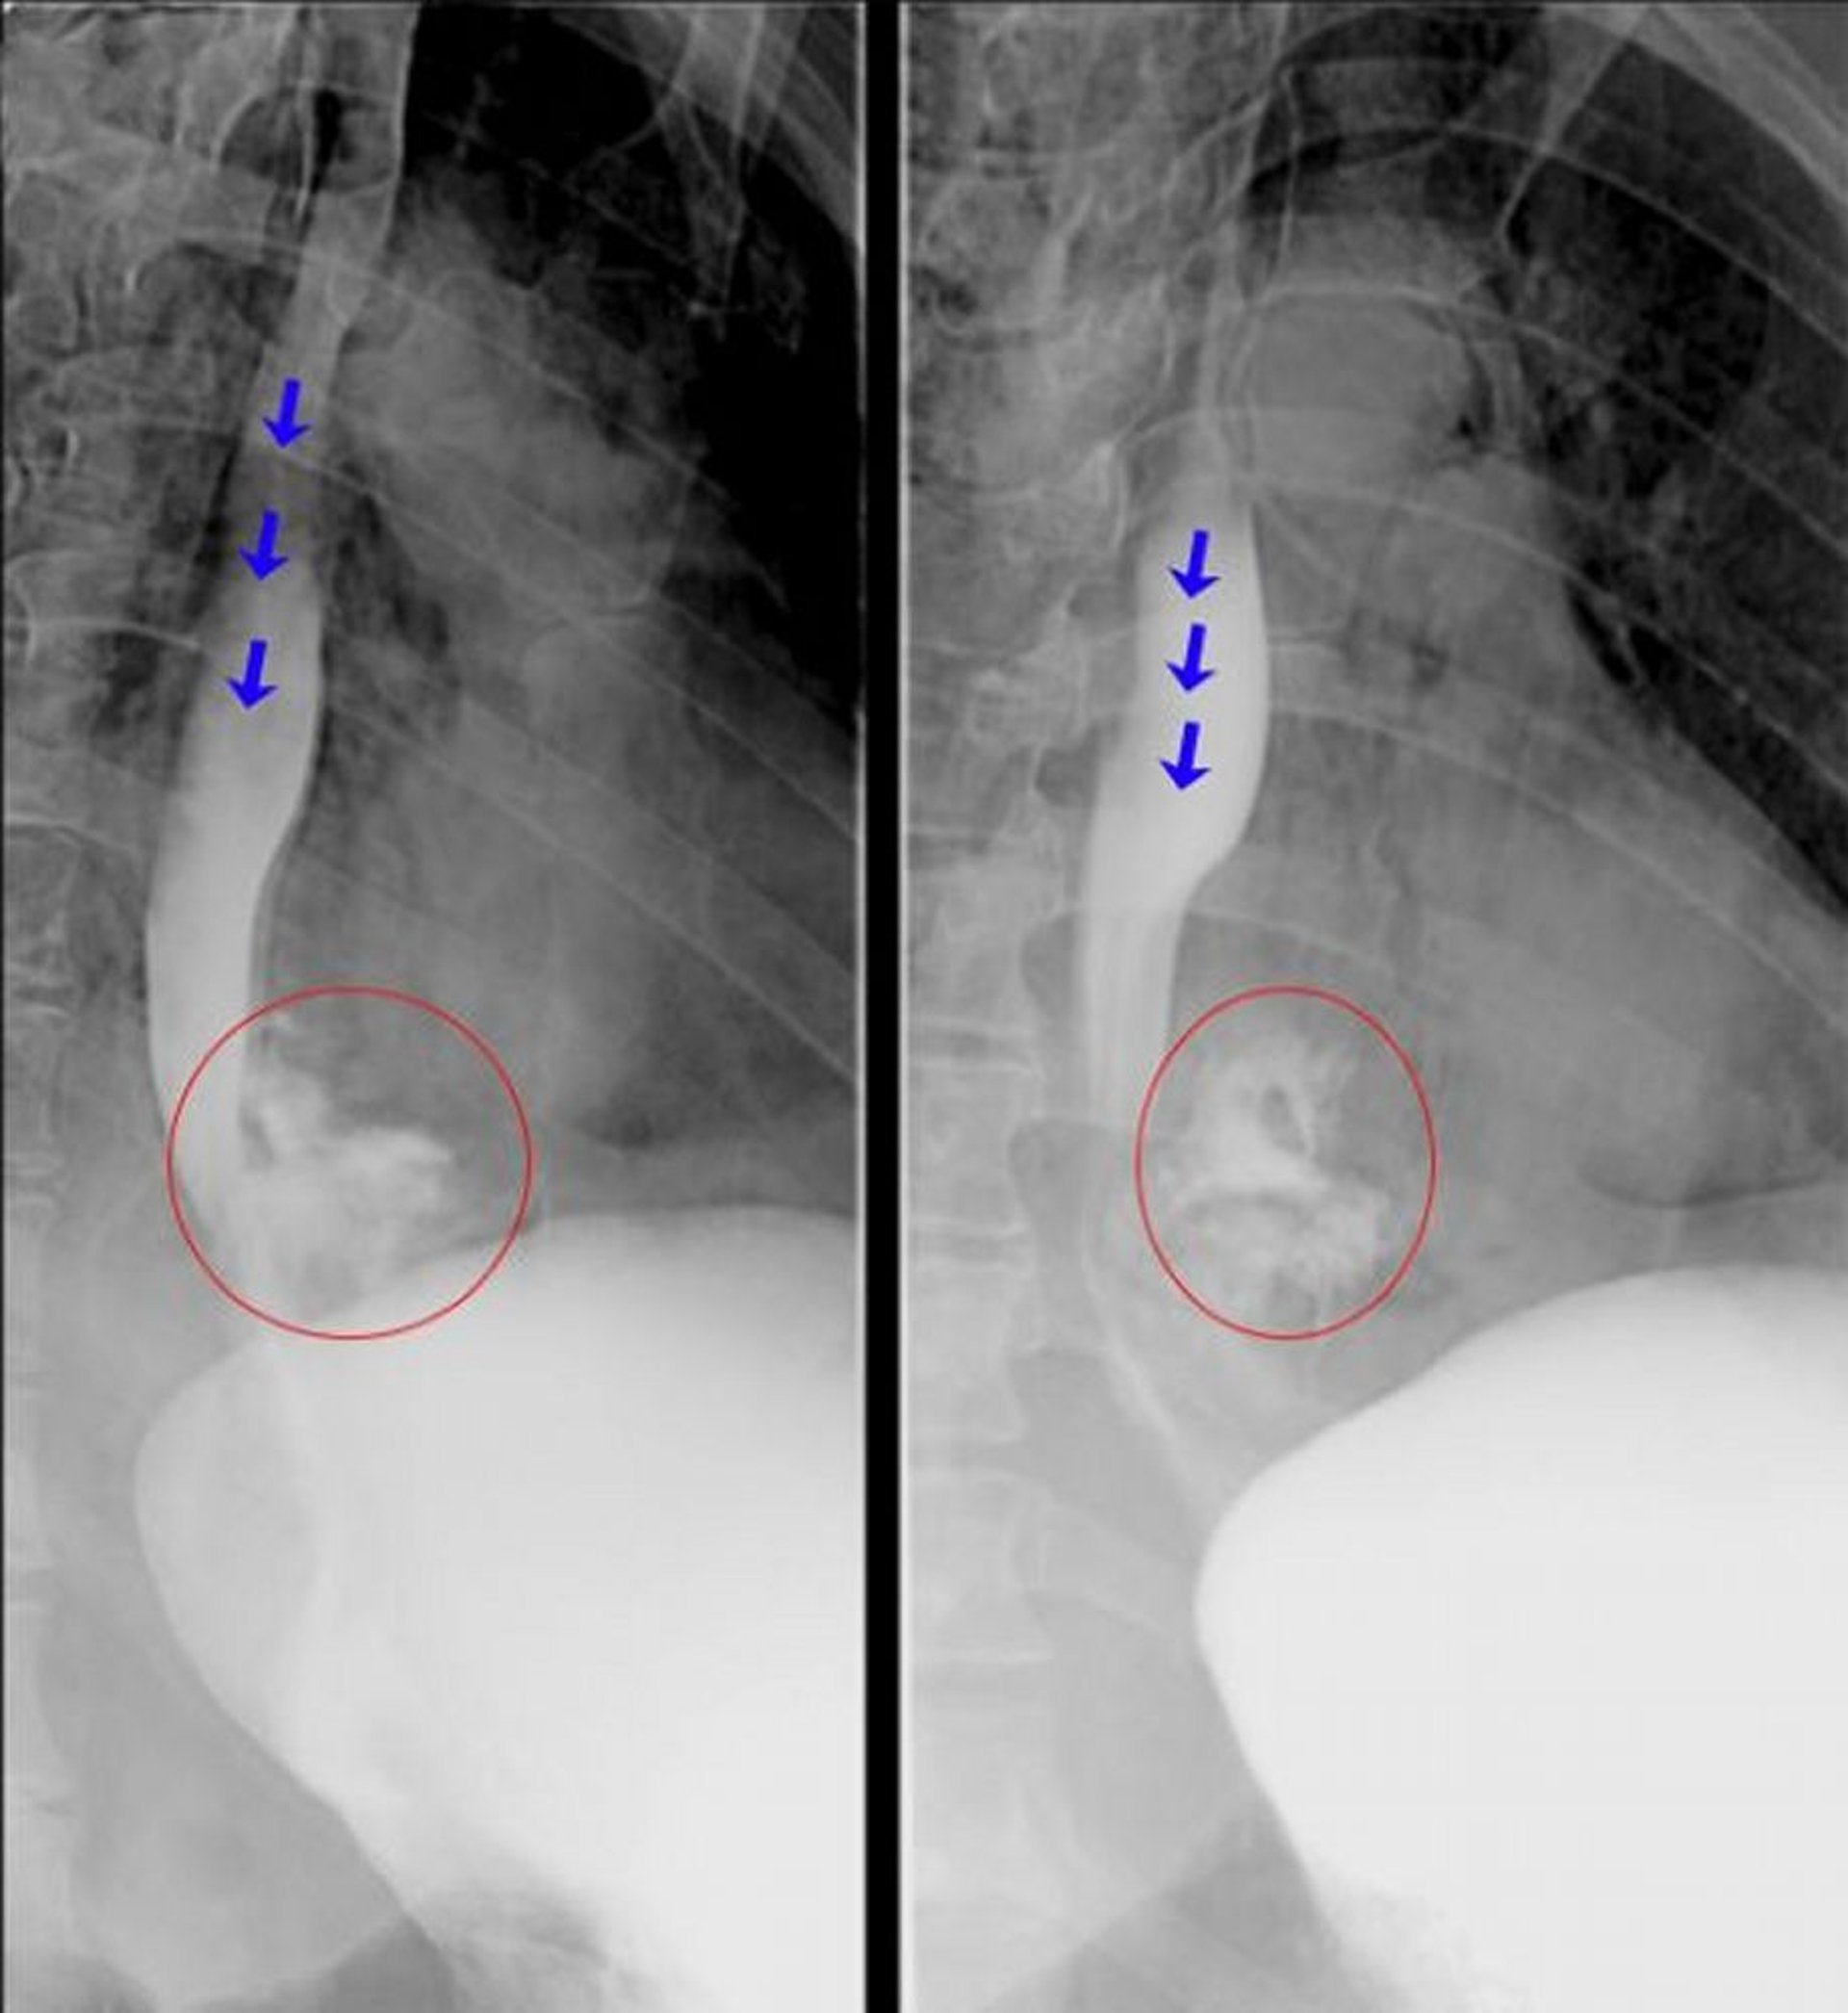

Эти рентгеноскопические эзофагограммы показывают явную экстравазацию контрастного вещества из дистального отдела пищевода, что согласуется с диагнозом перфорации пищевода. Синие стрелки указывают на контрастное вещество в просвете пищевода. Красными кружками выделено контрастное вещество, вышедшее из пищевода.

© Springer Science+Business Media